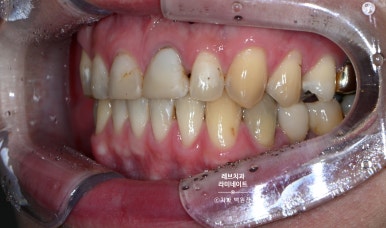

같은 사람임을 인증하기 위해서, 레브네이트 치료 받지 않은 어금니까지 보이는 사진을 첨부했습니다.

그리고 특별한 착시가 들어가 있는데요, 옆에서 보면 꽤나 송곳니가 넓어보이는 것을 확인하실 수 있을거에요. 심지어 좌우 사이즈도 좀 다르죠.

다만, 앞에서 보면 완전 대칭으로 보입니다! 앞에서 보이는 각도를 감안해서 만듦으로써 환자분이 갖고 있는 상황 내에서 최선의 결과를 내는 것.